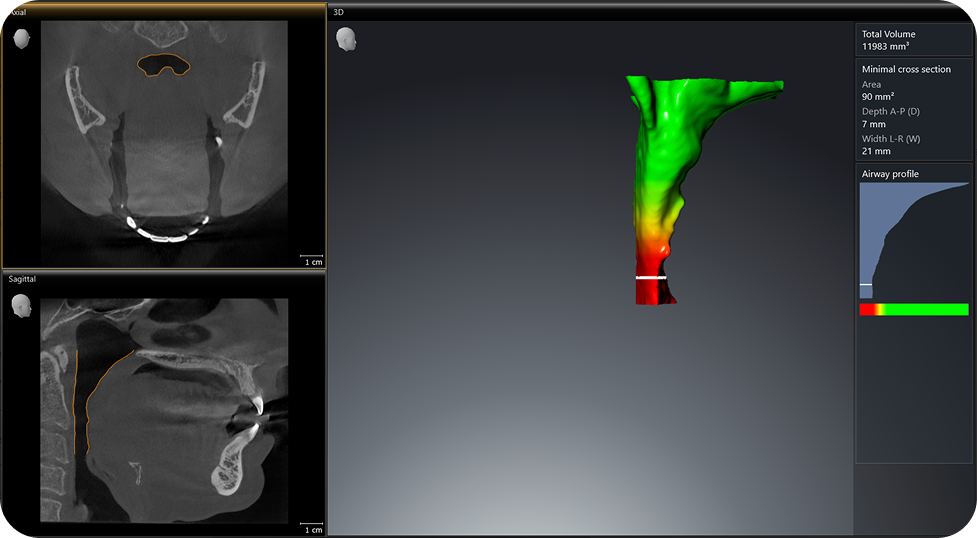

- At-home sleep study referral and advanced airway imaging